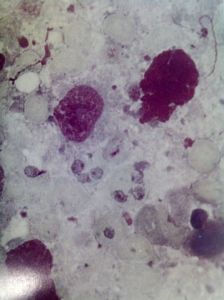

![]() |

| 心裡的角落 |